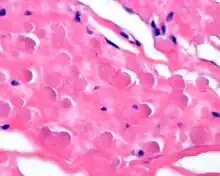

By microscopie view, there is an admixture of heavy dense bands of collagenous tissue dissected by fat and abnormal elastic fibers. The elastic fibers are often quite large and are easily identified. The elastic fibers are coarse, thick, and darkly eosinophilic, often fragmented into globules, creating a "string of pearls" or "pipe cleaner" appearance. Because of degeneration, the elastic fibers will appear as globules with a serrated or "prickled" edge.[4]